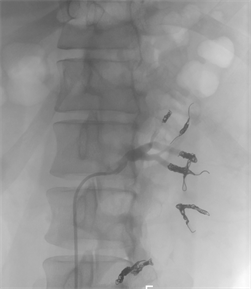

On the day before nephrectomy, catheter embolization of the left renal arteries was carried out by radiologists in order to decrease the size of tumor (Figure 4(a)). On the following day, radical nephrectomy and resection of the extended tumor in the IVC were performed through a median laparotomy. Although invasion of Gerota’s fascia was observed, there was no metastasis to the lymph nodes. After inspection of the IVC through a longitudinal incision, the cylindrical tumor tissue was found to occupy the entire left renal vein and IVC (Figure 4(b) and Figure 4(c)). The tumor was completely resected along with the wall of the left renal vein and the IVC directly closed using linear suturing. Computed tomography scanning performed immediately after the surgery found no new lesions in the pulmonary arteries.

Figure 4. (a) Catheter embolization of the left renal arteries; (b) The resected left kidney showing renal cell carcinoma; (c) Tumor tissue extending throughout the entire left renal vein and inferior vena cava (white arrow heads).